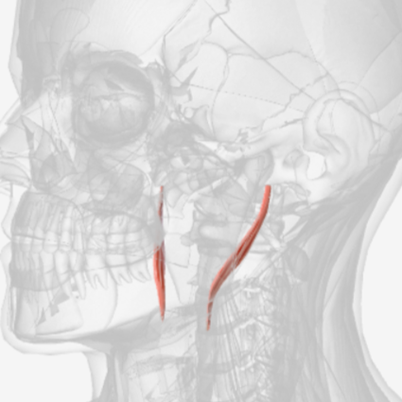

Middle pharyngeal constrictor

origin is on the horns of the hyoid and stylohyoid ligament, coursing up and back to the median pharyngeal raphe; function is to narrow the diameter of the pharynx

Middle Pharyngeal Constrictor

|  |  |

Middle pharyngeal constrictor

D

Middle pharyngeal constrictor

D

Middle pharyngeal constrictor

G

Middle pharyngeal constrictor

F